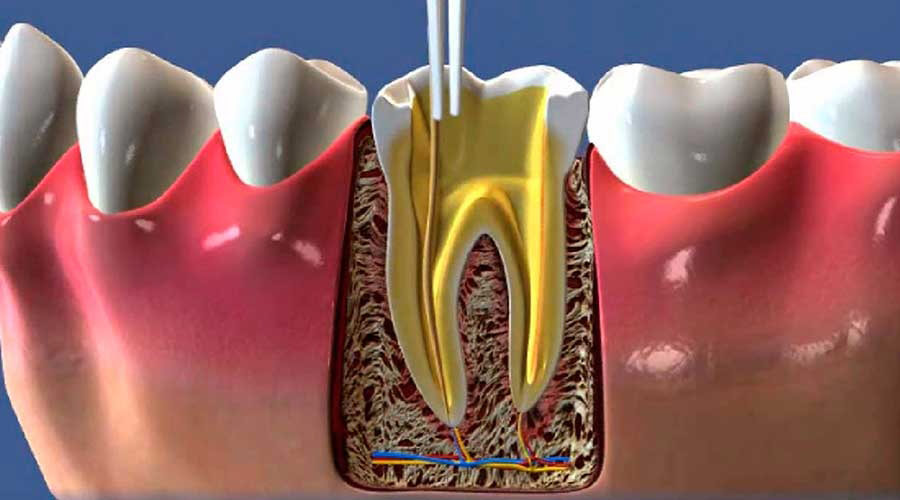

Endodontia

Especialidade voltada ao tratamento das patologias que acometem a polpa dental e os tecidos periapicais.

Procedimentos como a terapia endodôntica são fundamentais para a preservação de dentes que, de outra forma, seriam extraídos.